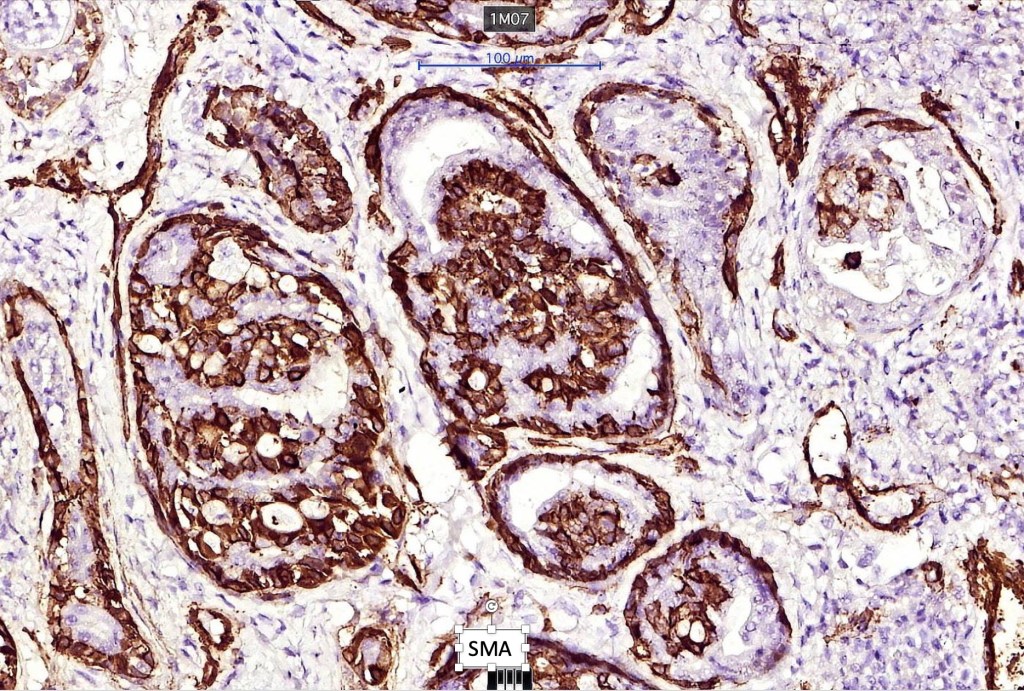

Immunohistochemistry

•Myoepithelial cells: p63, calponin, & SMA +ve

Immunohistochemistry from a case shared with me by Dr. Antonina Kalmykova except type IV collagen which was shared with me by Professor Mattheos Bobos